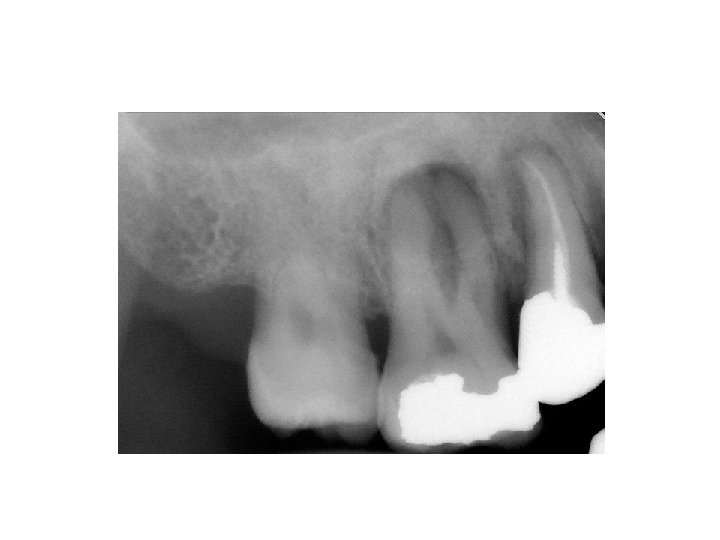

Granuloma periapicale • abgekapselte Ansammlung von Granulationsgewebe • Symptome: Keine Schmerzen, Devitalität des betroffenen Zahnes. • Röntgen: rundliche Form, scharfe Grenze, periapikale Aufhellung • Histologie: Cyst > 1 cm (Fluidum) Granuloma < 1 cm (Granulationsgewebe)

Parodontitis lateralis chronica • Es gibt Seitekanale nach mesiale oder nach distale Richtung. Die Veränderung erscheint neben der Wurzel. • Symptome: Keine Schmerzen, Devitalität des betroffenen Zahnes. • Röntgen: rundliche Aufhellung im lateralen Parodontium.

Falsch negative Diagnose • • • Foramen incisivum Foramen mentale Sinus maxillaris Foramen nasale Tuberkel von Pulpa